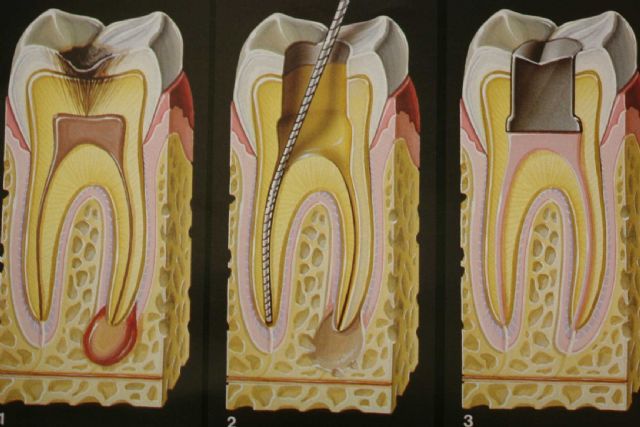

Endodonti (Kanal Tedavisi)

Enfekte olmuş dişleri kurtaran kanal tedavisi. Ağrısız ve konforlu tedavi süreci.